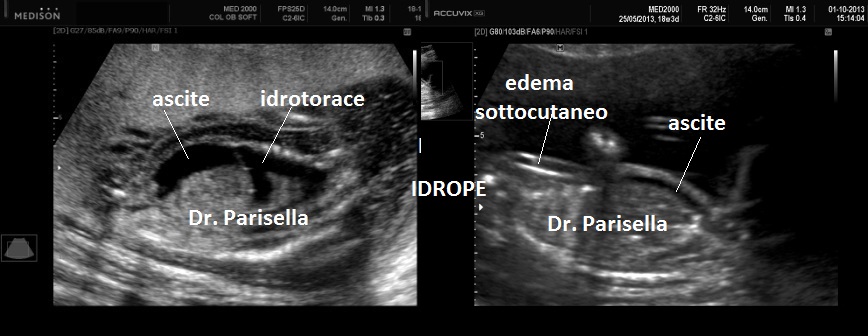

E' caratterizzata da grave ritardo di crescita intrauterino, grave microcefalia, lissencefalia tipo 3  e dismorfismi facciali consistenti in ipertelorismo, micrognazia, grave esoftalmo, anomalie auricolari, naso piatto; una caratteristica è l'edema spiccato che interessa cranio, gomiti, ginocchia, mani e piedi (si ha quasi l'impressione che le dita siano assenti); vi è inoltre assenza dei movimenti attivi fetali (SAF) e possono esservi contratture articolari (artrogriposi) caratterizzate da arti superiori ed inferiori in flessione.

4. edema spiccato,

5. assenza di movimenti attivi fetali (SAF),

9. idrope,

Caratteristica ai fini diagnostici la triade: IUGR, Esoftalmo spiccato, Edema fetale.